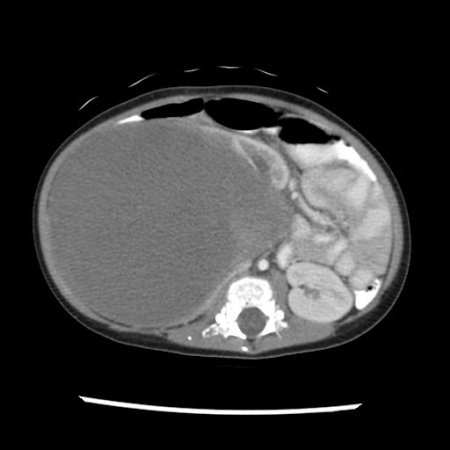

Рисунок 2. КТ: опухоль при поступлении. Клинически: при пальпации опухоль в проекции правой почки до 12 см в диаметре. Общеклинические исследования в пределах возрастной нормы. При КТ органов брюшной и грудной полости: КТ-картина объемного образования правой почки без признаков интрапульмональных метастазов (см. рис. 2). УЗИ брюшной полости: в проекции правой почки солидно-кистозное образование 101ґ114ґ99 мм, объемом 500 мл, васкуляризация активная, интактная часть почки 57ґ12ґ40 мм. Объемное образование правой почки — опухоль Вильмса. Предварительный диагноз: опухоль Вильмса правой почки, 2-я стадия.

Рисунок 3. Контрольная КТ: опухоль после предоперационной химиотерапии. Ребенку проведена предоперационная химиотерапия. На 5-й неделе лечения КТ-контроль показал уменьшение опухоли в размерах до 90ґ80ґ100 мм (см. рис. 3).